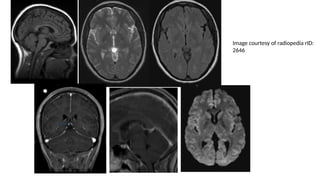

Pineoblastoma • They aresmall round blue cell tumours located in the pineal region. • They closely resemble (both on imaging and histology) like other blue cells like medulloblastoma and retinoblastoma. • They are the most aggressive (WHO grade 4) • They are typically found in young children, with only a slight female predilection

• 31.

• There isa well established association with hereditary retinoblastoma where • Trilateral retinoblastoma- Bilateral retinoblastoma and a pineoblastoma • Quadrilateral retinoblastoma- Bilateral retinoblastoma, pineoblastoma and a supracellar pineoblastoma

• 32.

CT Findings • Relativelylarge tumours • Slight hyperdense (high cellular tumor) • Classically, shows or "exploded" similar to pineocytomas ( In contrast, pineal germinomas tend to engulf pineal calcification)

• 33.

MRI Findings • Irregularmasses often with evidence of invasion into the adjacent brain • T1: Isointense to hypointense to adjacent brain • T2 • Isointense to adjacent brain • areas of cyst formation or necrosis may be present • T1 C+ (Gd): vivid heterogeneous enhancement

• 34.

• DWI/ADC- restricteddiffusion due to dense cellular packing • Central cystic necrosis is sometimes present and thus can roughly mimic a pineal cyst, although the latter should have a smooth, thin wall • Screening of the whole neural axis is necessary as CSF seeding is seen in 45% of cases.

• #30 highest grade tumour among pineal parenchymal tumours and are considered WHO grade 4 tumours (M:F 0.7:1; similar to other pineal parenchymal tumours), which is in contrast to the male predominance seen in pineal germinomas)

• #31 Trilateral retinoblastoma refers to the combination of retinoblastoma (usually bilateral) and pineoblastoma. This association highlights the close relationship between these highly aggressive small round blue cell tumors. Approximately 5-15% .

• #35 A large mass ( * ) centered on the pineal region elvates, splays and partially engulfs the internal cerebral veins (blue arrows). Pineal calcifications (red arrows) are best seen on CT and are located at the periphery of the mass.  Enhancing soft tissue is also seen filling the floor of the third ventricle (green arrows) and in the lateral ventricles (best seen in the left forntal horn - yellow arrow).

• #36  the pineal region shows a lobulated soft tissue mass lesion, it measures about 2.9 X 2.7 X 2.7 cm in its main diameters  the lesion shows mildly hypointense T1 and hyperintense T2 / FLAIR signal, with inhomogenous post-contrast enhancement the lesion shows mild restricted diffusion a suspected small signal void focus is seen at its peripheral anterior aspect of the lesion (which was evident on CT study that was available with the patient)  the lesion is seen compressing the superior portion of the cerebral aqueduct with moderate supratentorial hydrocephalus as well as transependymal CSF permeation mild downward herniation of the cerebellar tonsils is noted